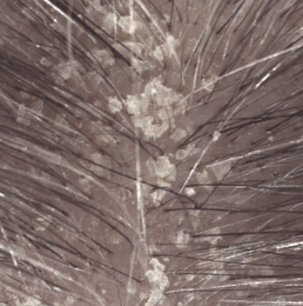

Actif kératolytique induisant une perte de cohésion significative au niveau du stratum corneum : desquamation des plaques épaisses sur le cuir chevelu.

Résultats d'efficacité

Induration à 1 mois (3)

(1) Etude clinique auprès de 54 sujets présentant un psoriasis du cuir chevelu léger à modéré. Phase d’attaque de 4 semaines : 3 shampoings par semaine.

(3) Évaluation clinique de l’induration des plaques à J29.